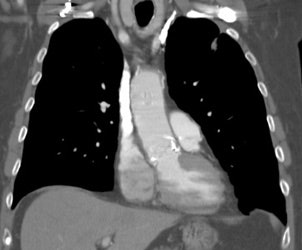

|

Normal vascular activity: Faint activity can be seen in the descending thoracic aorta (black arrows) |

Vascular graft activity: The patient below had a prior graft repair of an ascending aortic aneurysm. Tracer uptake can be seen in the ascending aortic graft (black arrows). The patient also has a left upper lobe lung cancer (red arrows). |

|